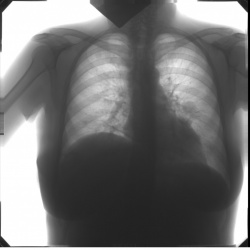

Девочка. Давно болеет. После рентгена КаТали уже. Пневмония движется. Коллеги, подскажете направление?.. С пятном справа - первый, контроль - без него.